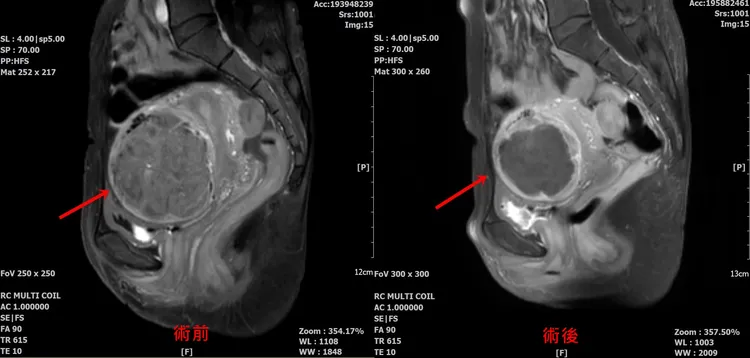

術前術後比較。院方提供

童綜合醫院婦產部劉錦成主任表示,黃姓患者術後恢復良好,1周後回診腰痠、腳痛的狀況有明顯改善;1個月後回診,上班久站也沒有發生到腰痠與腳痛等不適症狀;2個月左右再回診,進行核磁共振檢查,明顯發現肌瘤細胞已經壞死,並且壞死細胞已逐漸被身體吸收代謝,子宮肌瘤明顯變小,血紅素指數回升到11.4gm/dL。